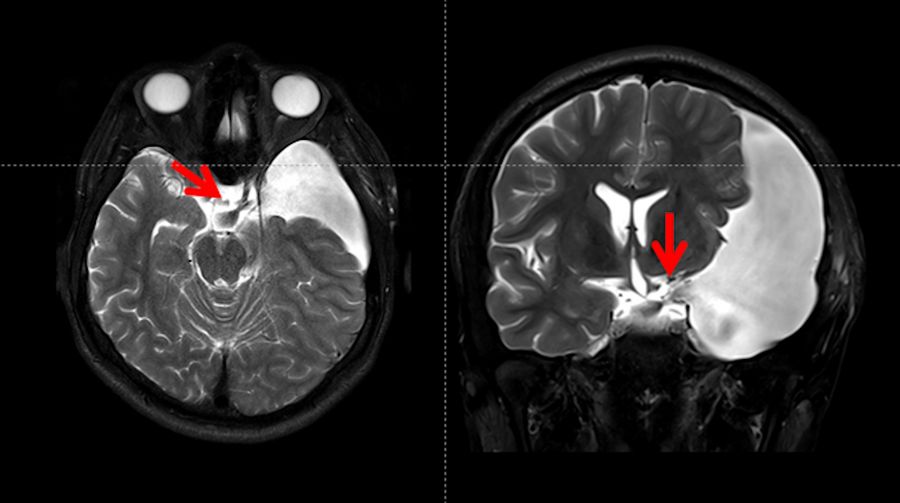

The T2WI revealed a large arachnoid cyst (represented by red arrows) on the left side with a hyper-signal when compared to the brain, including a similar signal compared to the cerebral spinal fluid.

Fig. 3: T2 weighted MRI showed a large arachnoid cyst (red arrows), Galassi III with a hyper-signal compared to the brain, and iso-signal when compared to the cerebrospinal fluid inside the ventricles. This cyst is compressing the adjacent brain and is not communicating with the Sylvian, carotid, and optic-Chiasmatic cisterns).